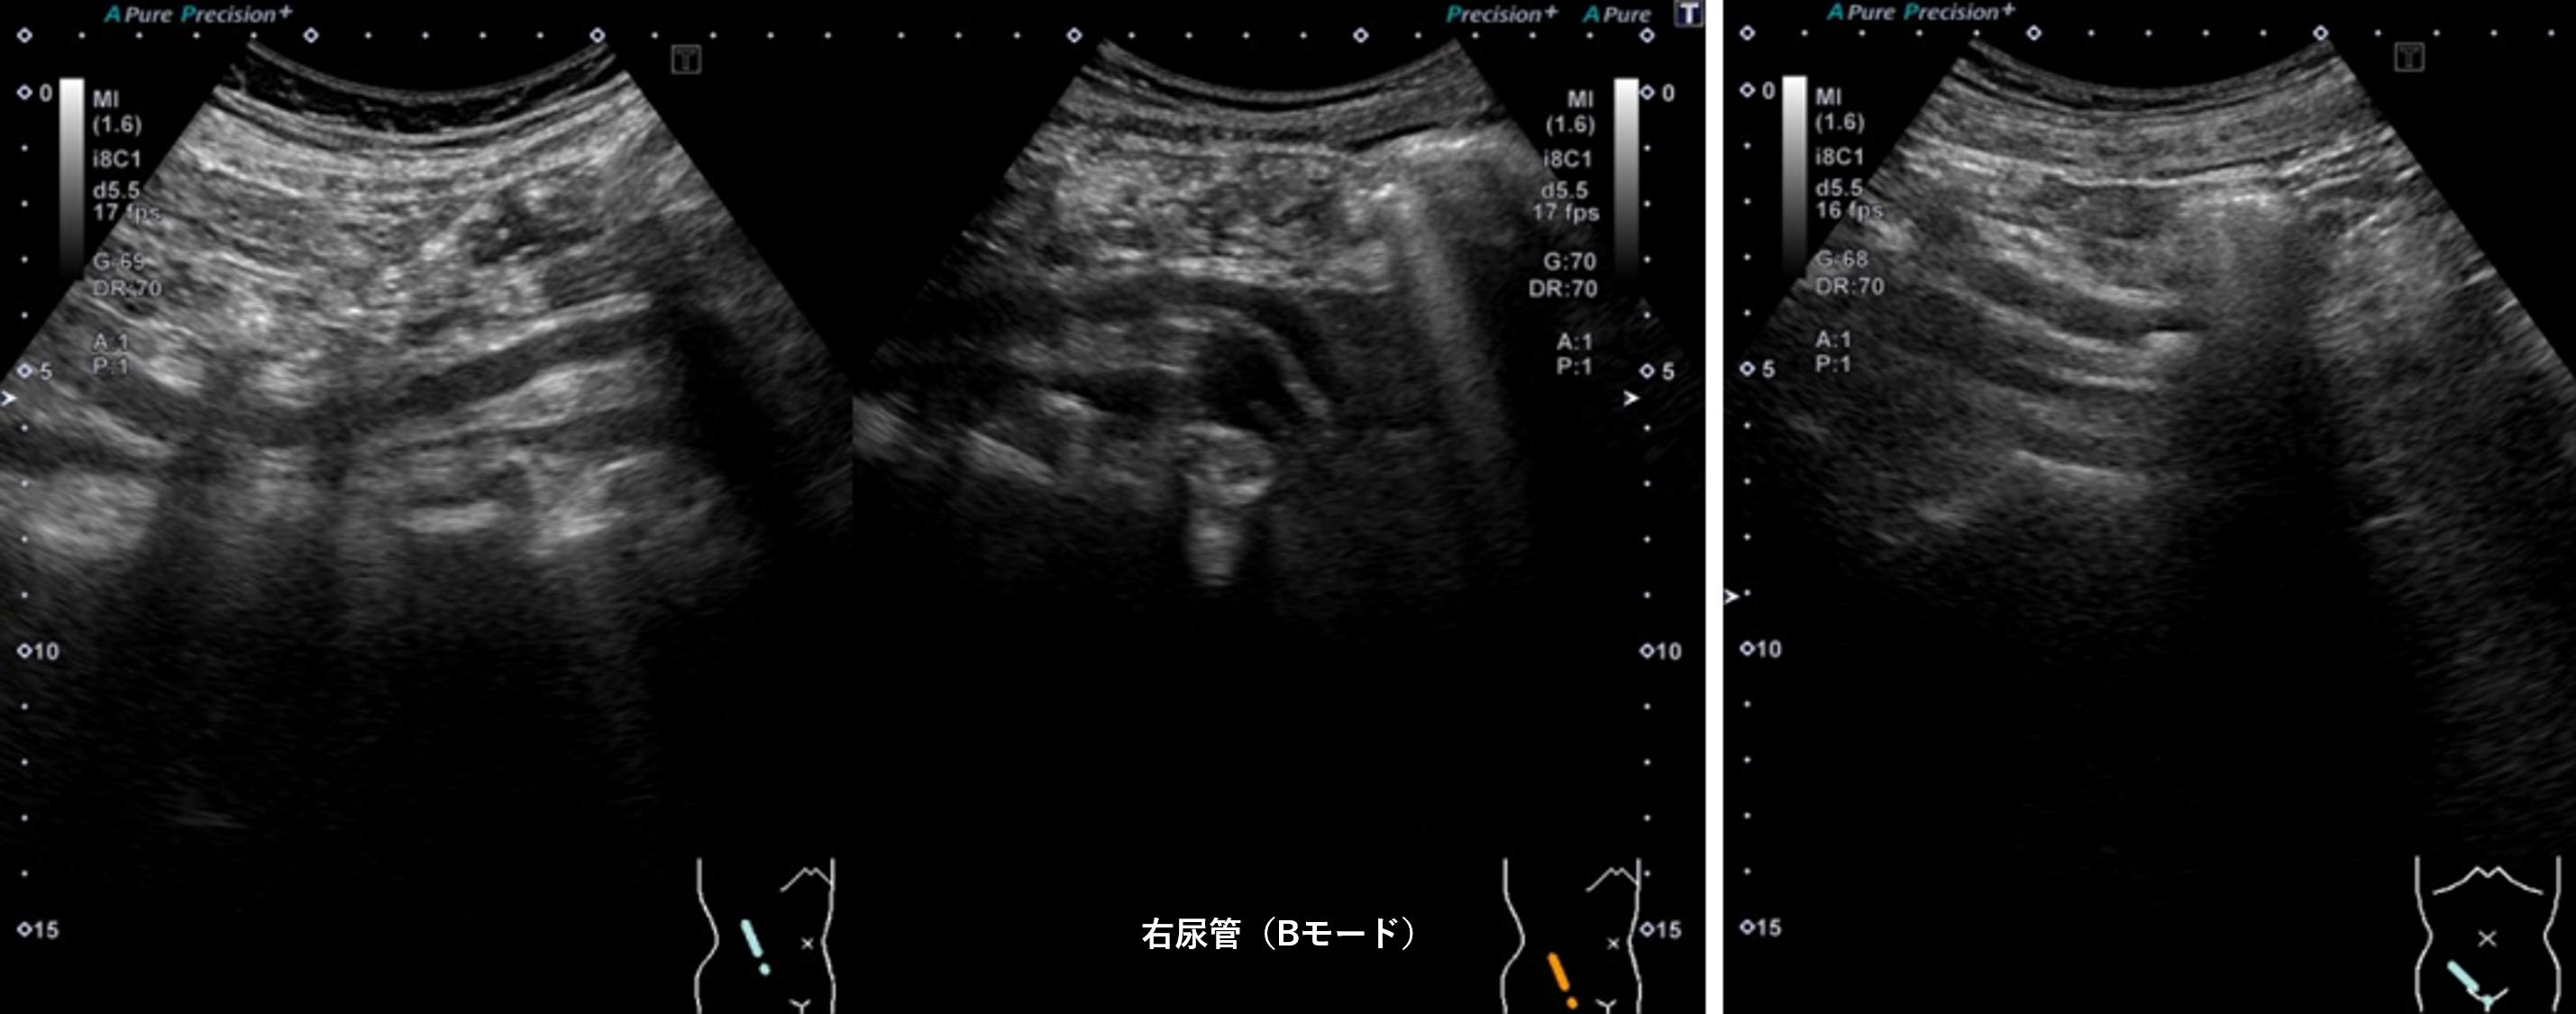

腹部超音波2 動画3 右尿管(No18-19_C)

腹部超音波2 動画3(No18.19_C)

① 右尿管内に充実性腫瘍像を認める

④ 右腎の腎盂拡張および右尿管拡張を認める

⑤ 右腎中心部エコー内に無エコー領域を認める